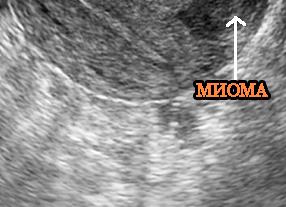

Если при УЗИ был обнаружен миоматозный узел, то с большой долей веероятности можно говорить о наличии заболевания.Как правило, миома это округлый гетерогенный по структуре объект, обладающий на УЗИ четким и ровным контуром, ослабляющим ультразвуковой сигнал.

Эхопризнаки миомы матки и структура такого образования во многом зависят от того, из каких тканей оно состоит и где располагается. Фибромы будут выглядеть более «светлыми», гиперэхогенными. Лейомиомы за счет преобладания низкодифференцированных гладкомышечных волокон в их составе будут давать более однородную, гипоэхогенную картину.

Леймомиома обнаружена у пациентки 46 лет, которая жаловалась на вагинальное кровотечение. На снимке хорошо видно изоэхогенное образование.

Фото 1. Как выглядит миома матки на УЗИ.

Врач-сонолог определяет миому как округлый объект с гетерогенной структурой и чёткими границами, делающими сигнал датчика слабее.

Эхогенность и структурные особенности миомы напрямую зависят от места возникновения опухоли и от типа тканей, её образующих. К примеру: